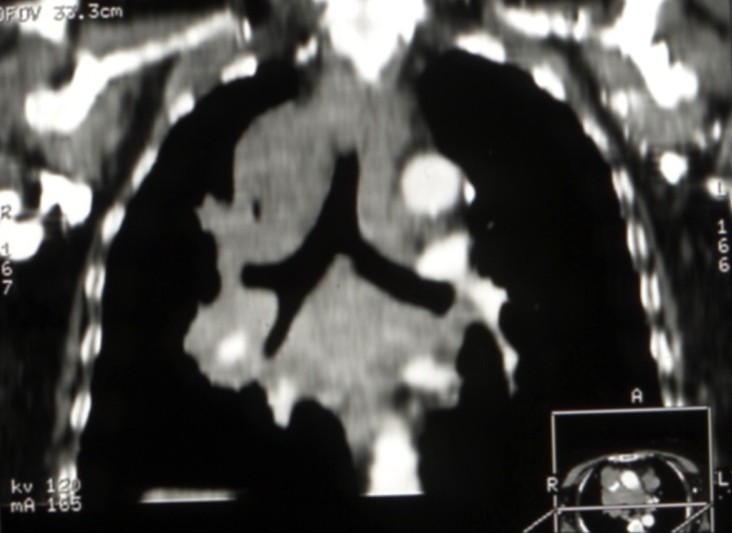

Cancers bronchiques